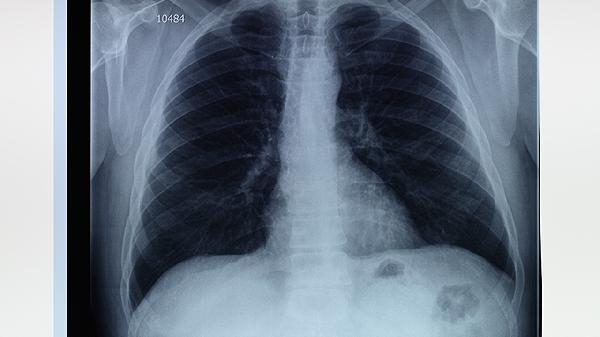

1、肺大泡是肺泡壁破裂后形成的异常扩张,酒精会刺激呼吸道黏膜,导致炎症加重,增加肺大泡破裂的风险。长期饮酒还可能削弱免疫功能,增加肺部感染的可能性,进一步加重病情。

2、肺大泡患者应严格戒烟戒酒,烟酒中的有害物质会直接损伤肺部组织,加速病情恶化。同时,需避免接触空气污染物和刺激性气体,以减少对呼吸道的刺激。

3、控制感染是肺大泡治疗的重要环节,患者应注意保暖,避免感冒和呼吸道感染。必要时可遵医嘱使用抗生素或抗炎药物,以预防或治疗感染。

4、对于较大的肺大泡或反复破裂的患者,可考虑手术治疗。常见手术方式包括肺大泡切除术、肺减容术和胸腔镜手术,具体方案需根据病情和医生建议选择。